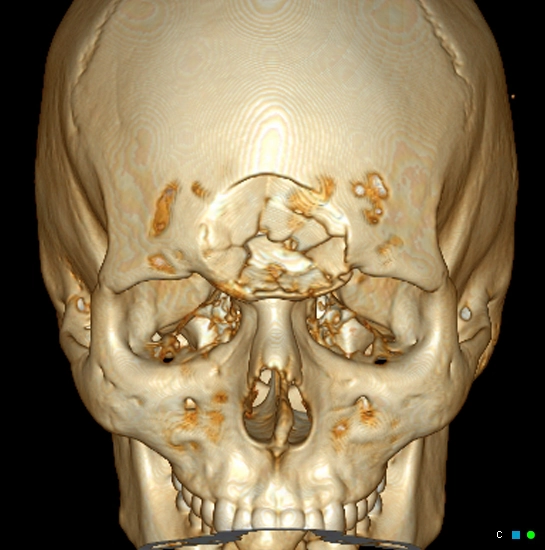

• Chấn thương hàm mặt

• Gãy xương phức tạp

Gãy xương Le Fort (Le Fort fracture classification)